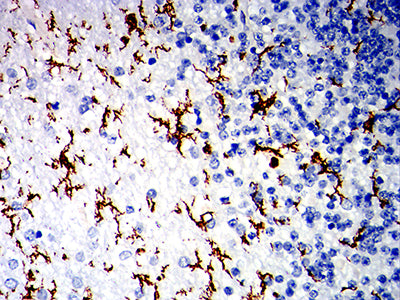

分类: 科研抗体货号: 32297别名: IGA; MB-1应用: IHC,IF,FCM反应种属: Human